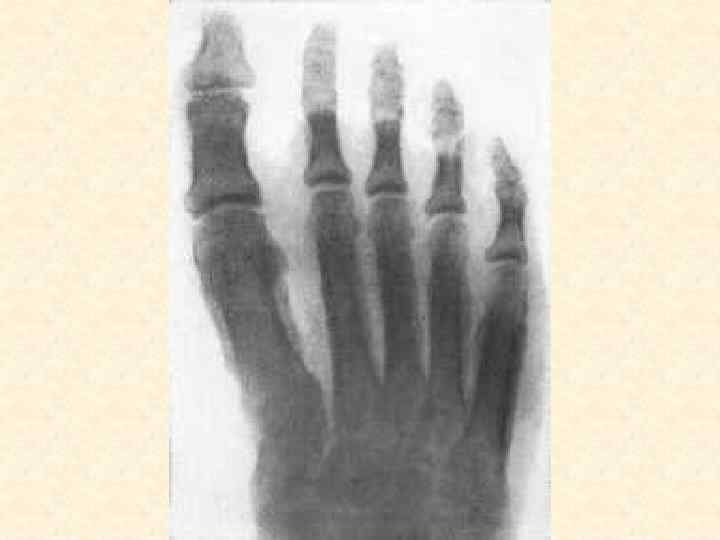

Заболевания, поражающие костную систему • • • Остеомиелит, артрит Артроз Остеопороз Остеомы Переломы костей

Методы диагностики поражения опорной системы человека 1. 2. 3. 4. Рентген, КТ, Радиоизотопная диагностика, Остеоденситометрия